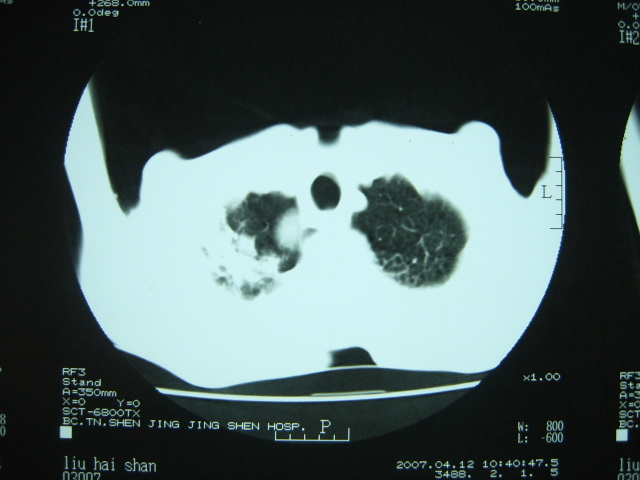

男74岁,咳嗽,寒战,低烧。有糖尿病史。

两肺结核,空洞形成,左下肺肺段隔离症待排

两肺结核,左下肺空洞性病变,结核性?炎性?癌性?抗炎治疗后复查。

两肺结核,左下肺大片实变,内见空洞性病变,壁不规则,结合糖尿病史,考虑:结核性?霉菌性?建议结合实验室检查或治疗后复查。